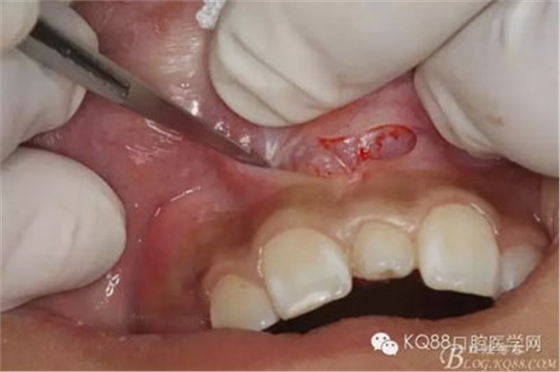

圖4.局部無(wú)痛浸潤(rùn)麻醉下。行唇側(cè)弧形切口